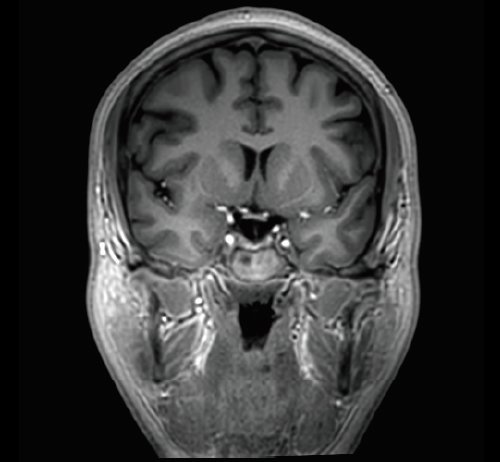

Der Vantage Galan 3T von Canon Medical Systems bietet Ihnen und Ihren Patienten eine neuartige Erfahrung in der Magnetresonanztomographie. Der Vantage Galan 3T legt sein Augenmerk auf das positive Patientenerlebnis, eine hohe Bildqualität und einfache klinische Arbeitsabläufe.

KI-optimiertes Arbeiten und modernste 3T-Technologie machen den Vantage Galan 3T von Canon Medical aus. Canons KI-Anwendung AiCE, kurz für Advanced intelligent Clear-Imagequality Engine, entfernt intelligent das Rauschen und führt zu einer Verbesserung des SNR (Signal-Rausch-Verhältnis). Mit Hilfe der Deep Learning Technologie gelingen besonders klare und deutliche Bilder. Insgesamt ermöglicht die KI-Unterstützung des Vantage Galan 3T somit nicht nur eine höhere Auflösung der Bilder, sondern verkürzt in vielen Fällen auch die Aufnahmezeit.